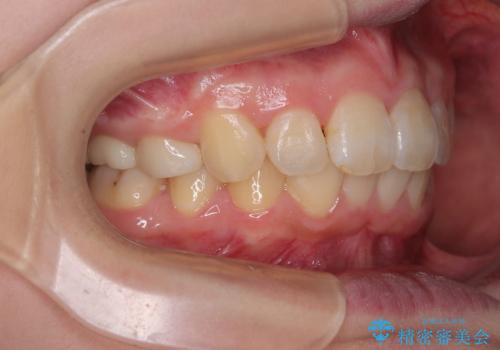

矯正治療後には、上顎欠損部をオールセラミックブリッジにて補綴治療を行うこととしました。

予想通りに治療は困難を極め、その上途中来院されない時期があったため、非常に長期間に及びましたが、周囲の方々が驚愕するほど口元の印象を改善することができました。